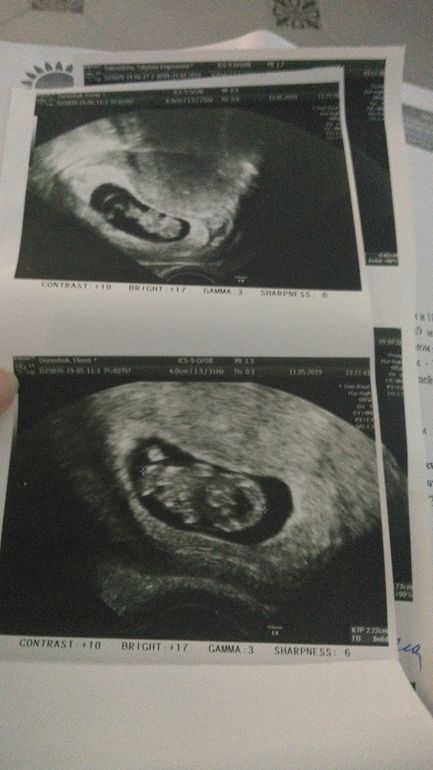

Девочки, кто уже увидел своих малявок?) 9 недель +

Мы уже большие 😅почти 3 см...скорее б к врачу, чтобы стать официально пузатой 😂

Ой какое счастье, увидела и расплакалась, я от всего плачу в данный момент😍.

У меня на 5+1 только точку видно было, три дня назад, вот жду тоже через 11 дней УЗИ, так надеюсь увидеть.

Какие хорошенькие!))) мы сегодня тоже на УЗИ были, срок 7.4 неделек, 1см🌸 растите здоровенькими!